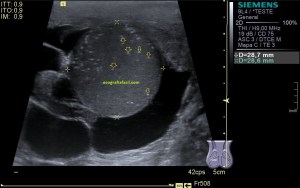

En esta última imagen te muestro la angiogénesis o neovascularización. Existe un aumento de aporte sanguíneo para reparar aquel tejido que está dañado. Esta angiogénesis o aumento de vascularización y por tanto Doppler podría ser secundario a un proceso de reparación mal gestionado por el tejido. Esta angiogénesis también podría estar en relación con aumentos del dolor en la zona y no significa que la patología cure antes. Gracias Javier. Gracias Amigo.